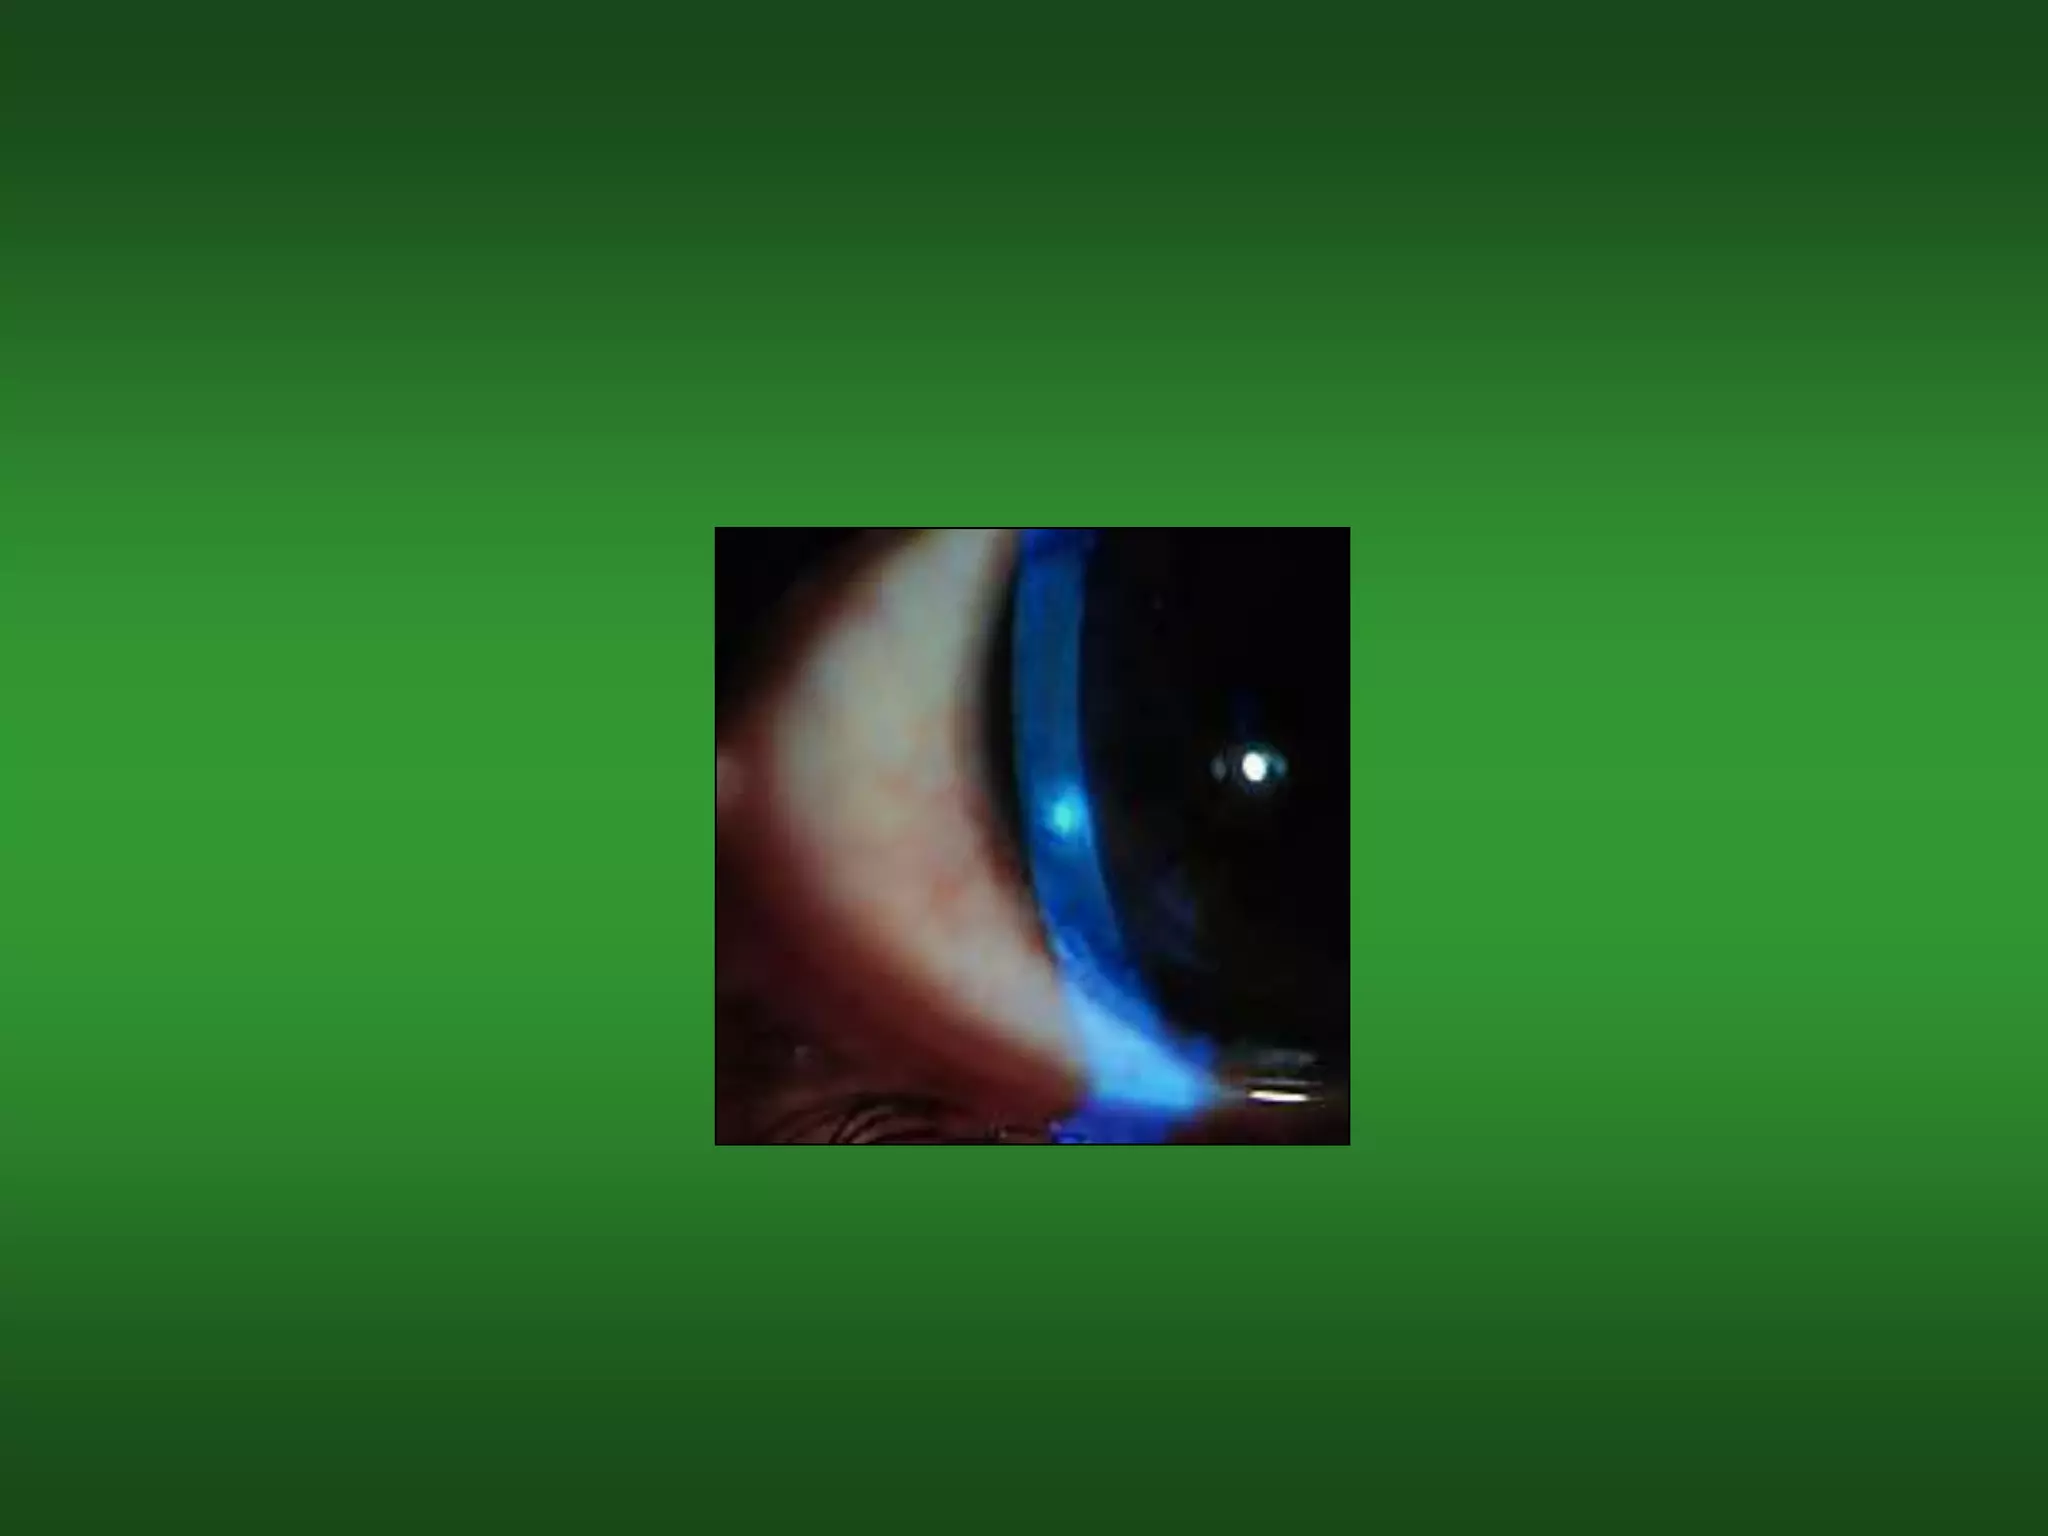

Vascularization(혈관신생)

• In most cases, vascularization is

• Vascularization can be graded according to

the number of quadrants and the extent to

원인

• Long-term wear of any soft lens, but

진단

• Varying degrees of vessels encroaching into

– Grade 1: Sectorial or circumlimbal vessel

extension less than 0.5 mm, or 1 or 2 vessels

extending less than 1.5 mm into cornea.

– Grade 2: Sectorial or circumlimbal vessel

extension 0.5 to 1.5 mm into cornea.